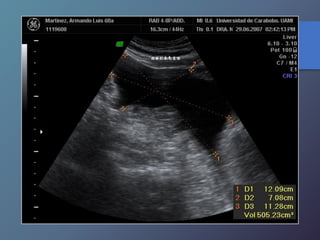

Neoplasias Hepáticas Malignas

Carcinoma Hepatocelular

• Antecedente de hígado cirrótico

• Relación 5:1

• Puede aparecer solitario, nódulos

múltiples o infiltración difusa.

• Ecograf. Similar a mt, infiltr. Grasa focal

hemangioma cavernoso

• Invasión a vena porta

• Alfa feto proteína elevada

• Variable desde mas hipoecoicas hasta complejas o

Hiperecogénicas.

• Los chc pequeños son hipoecoicos, con halo periférico

fino que Corresponde a la capsula.

• Los chc de mayor diámetro, tienden a ser Heterogéneas,

complejas.

• Son hipervasculares, con vasos dismórficos.

Características Ecográficas

Neoplasias Hepáticas Malignas CarcinomaHepatocelular • Antecedente de hígado cirrótico • Relación 5:1 • Puede aparecer solitario, nódulos múltiples o infiltración difusa. • Ecograf. Similar a mt, infiltr. Grasa focal hemangioma cavernoso • Invasión a vena porta • Alfa feto proteína elevada

Carcinoma Hepatocelular • Variabledesde mas hipoecoicas hasta complejas o Hiperecogénicas. • Los chc pequeños son hipoecoicos, con halo periférico fino que Corresponde a la capsula. • Los chc de mayor diámetro, tienden a ser Heterogéneas, complejas. • Son hipervasculares, con vasos dismórficos. Características Ecográficas